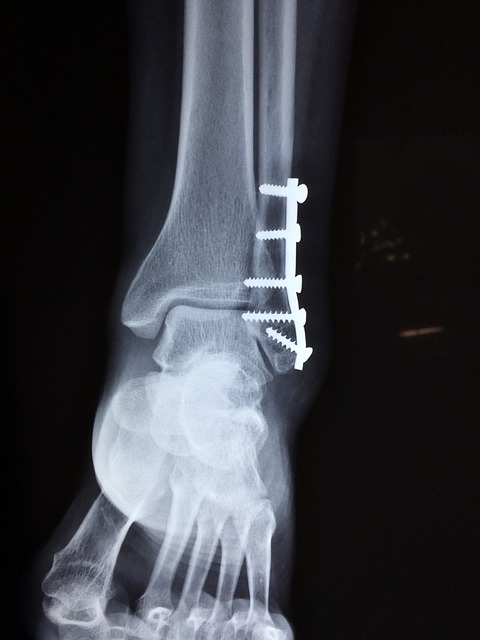

5. 발목 골절

발에 금이가 거나 골절된 경우 통증을 유발할 수 있습니다. 운동을 하거나 걷다가 발을 잘못 접질릴 때 발목 인대가 늘어나거나 뼈에 이상이 생겨 통증을 유발하게 됩니다. 발목에서 시작된 통증이 발뒤꿈치까지 이어질 수 있습니다. 발목이 골절된 경우에는 서있기도 힘들고 손으로 누를 때에 심한 통증을 유발하게 됩니다.